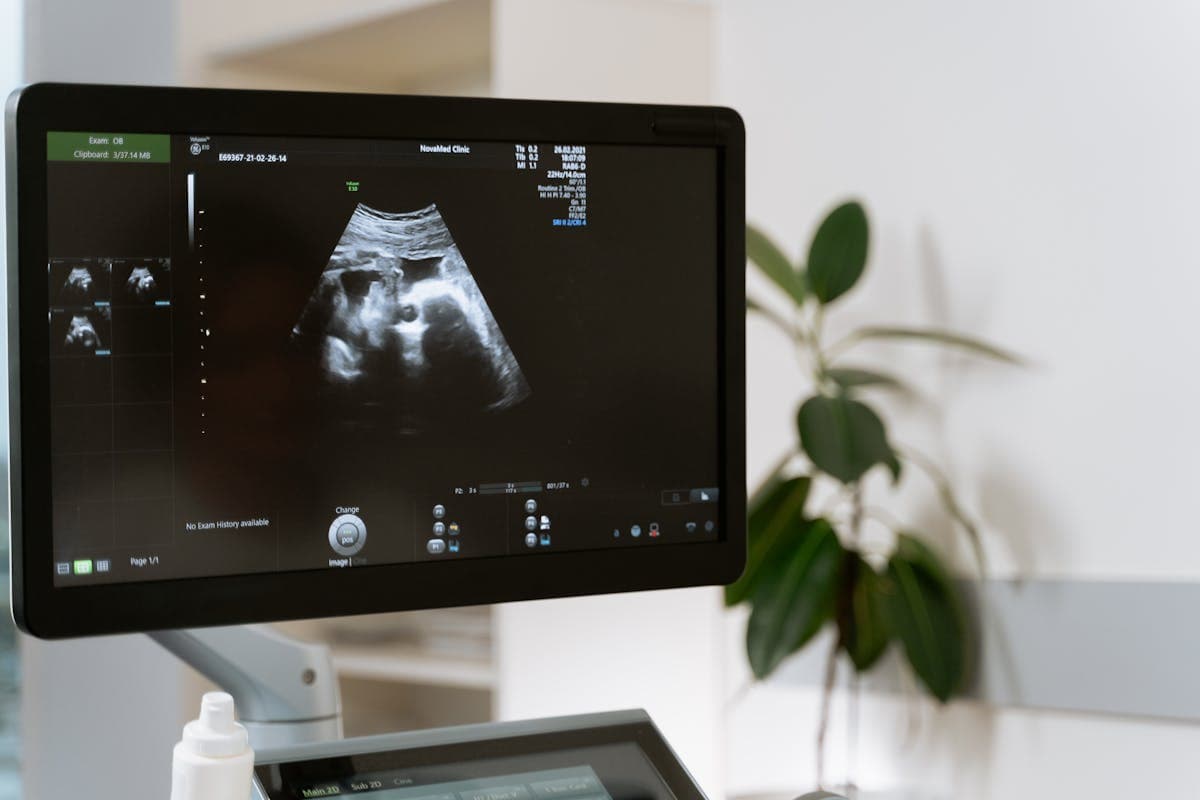

Ultrasound scans are a routine part of pregnancy care in Malaysia, but many parents do not realise that the purpose and focus of scans changes significantly across the three trimesters. Understanding what each scan is looking for — and why — can help you feel more prepared at every stage.

In the first trimester (weeks 1 to 13), ultrasound is primarily about confirming and dating the pregnancy. The dating scan checks that the pregnancy is inside the uterus, confirms the baby's heartbeat, and measures the baby to establish your due date. This is also when the nuchal translucency (NT) scan is performed between 11 and 14 weeks, screening for chromosomal conditions. First-trimester scans are sometimes done transvaginally for clearer images, especially early in the pregnancy.

The second trimester (weeks 14 to 27) is when the most important structural assessment takes place. The detailed anomaly scan at 18 to 22 weeks examines every major organ system in the baby's body. This is the scan where the quality of the operator matters most — an MFM specialist like Dr. Kartik, with advanced fetal imaging training, is best placed to perform and interpret this examination. The second trimester is also when growth patterns begin to be tracked and when the placenta's position is assessed.

In the third trimester (weeks 28 to 40), ultrasound shifts focus to growth and wellbeing. Growth scans measure the baby's estimated weight, check the amniotic fluid volume, and assess blood flow using Doppler studies. These scans are particularly important for pregnancies with gestational diabetes, hypertension, or other risk factors. The baby's position is also checked — whether head down, breech, or transverse — which affects the delivery plan.

Doppler ultrasound, used mainly in the second and third trimesters, measures blood flow in the umbilical artery, middle cerebral artery, and uterine arteries. Abnormal Doppler results can indicate that the baby is not getting enough nutrients or oxygen, prompting closer monitoring or earlier delivery. This is a specialised assessment that benefits from MFM expertise.